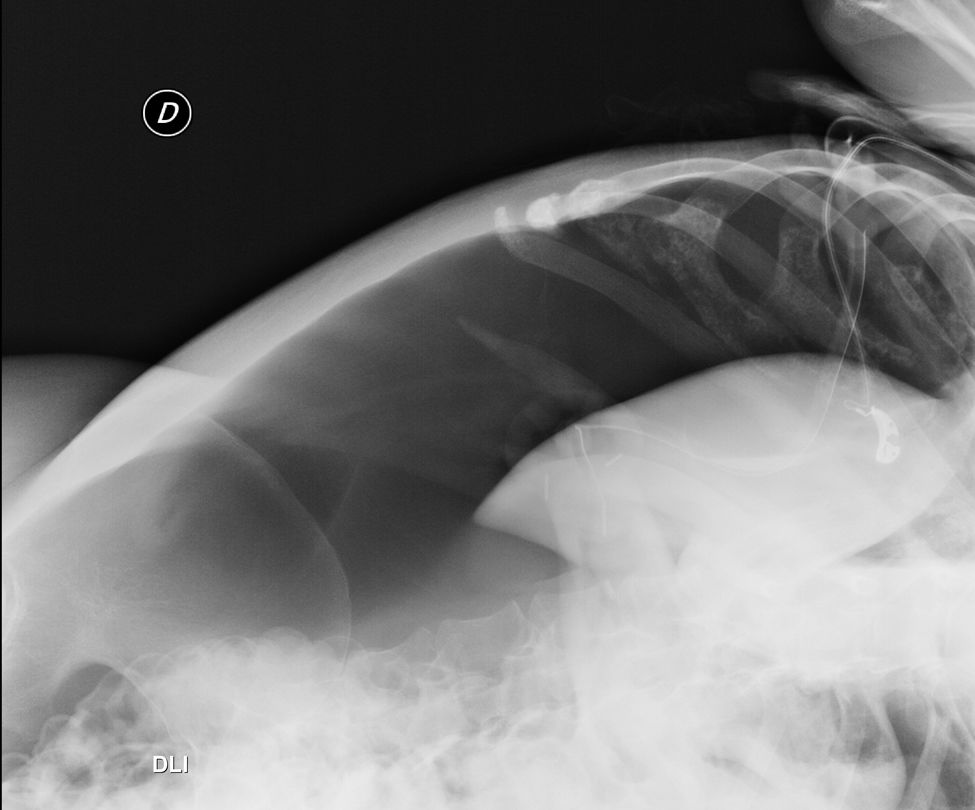

Pneumoperitoneum secondary to gastrostomy is a rare, usually benign complication, often due to air insufflation. It can occur after both endoscopic and radiological techniques, though less frequently with the latter. Percutaneous radiological gastrostomy is preferred in neuromuscular patients where deep sedation poses respiratory risks. We report a case of a Duchenne muscular dystrophy patient on non-invasive ventilation who developed symptomatic pneumoperitoneum, likely exacerbated by aerophagia. We propose minimally managing this with a semi-permanent percutaneous drain, allowing continued ventilatory support until resolution.